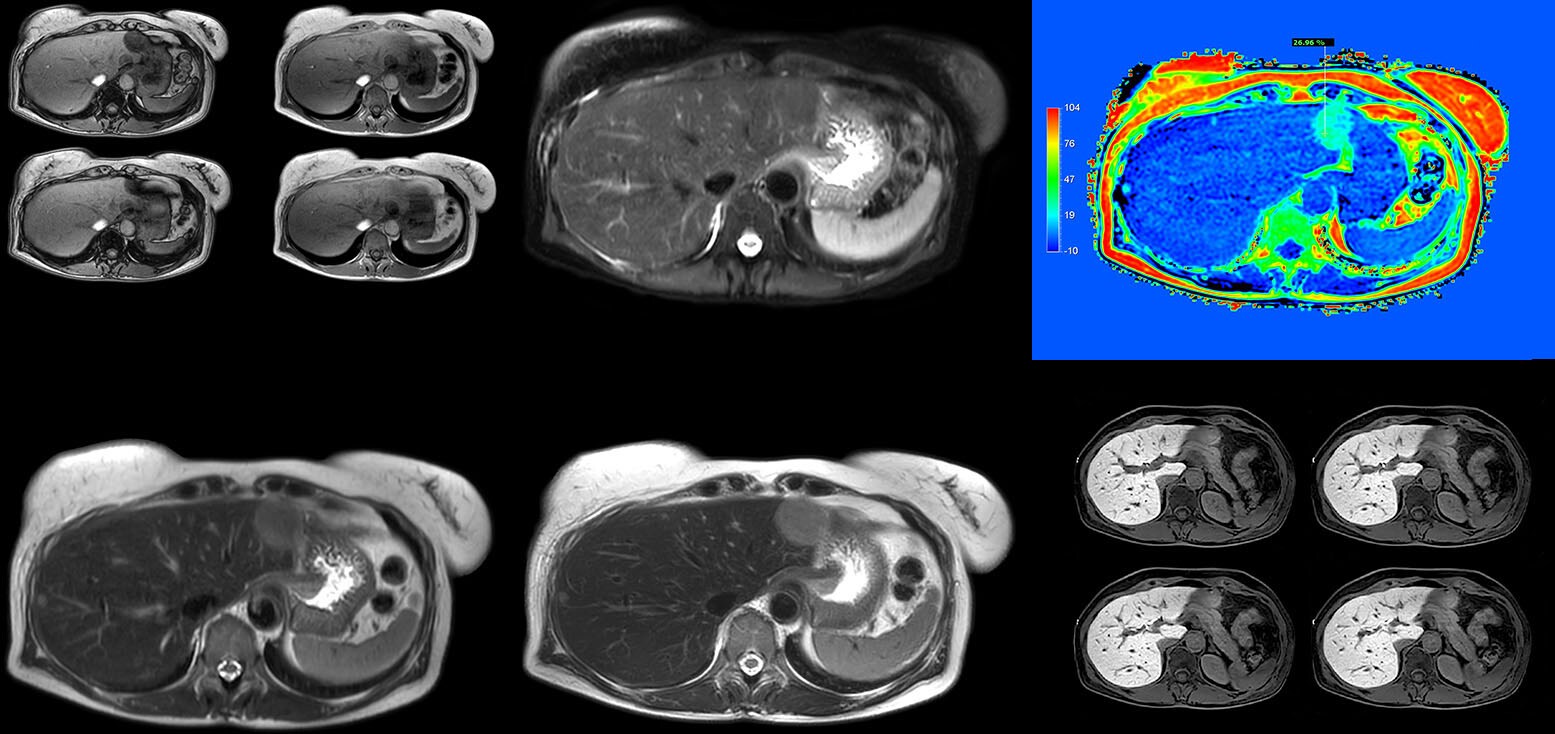

Patient-centric MRI equipment and solutions

Ultimate precision at maximum speed with Dual AI

Take the leap forward with SmartSpeed Precise, the next generation acceleration technique that expands the proven Compressed SENSE and SmartSpeed technologies with a unique integrated Dual AI innovation, providing ultimate precision at maxiumum speed.

Automated patient-centric MR workflow powered by AI

Support your staff with a workflow solution that allows them to focus less on technology and more on the patient while achieving high productivity with MR Smart Workflow.

Clinical cases from nearly every anatomy

Explore 200+ clinical cases and download exam cards from peers around the globe, showcasing how Philips MR technology enhances your imaging capabilities.